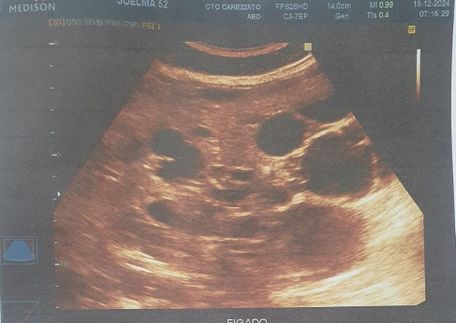

Foi realizado exame de imagem (21/10/2024), ultrassonografia abdominal com os seguintes achados (figura 1.1, 1.2, 2 e 3) Exames laboratoriais (21/10/2024): Acido úrico 2 mg/dl, Bilirrubina total 0,37 mg/dl, Bilirrubina direta 0,18 mg/dl, Bilirrubina indireta 0,19 mg/dl, TGP 21 u/l, TGO 16 U/L, Uréia 34 mg/dl, Creatinina 0,51 mg/dl, Sorologia para hepatite B, C não reagente.

Figura 1.1 e 1.2: identificando fígado de contornos irregulares, parênquima heterogêneo, ecogenicidade aumentada, trama vascular diminuída e volume aumentado, múltiplos cistos no parênquima hepático, o maior no lobo esquerdo medindo 8.9 cm x 7.0 cm.